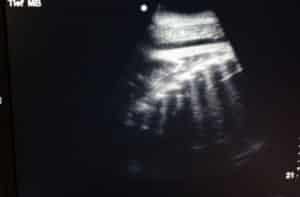

La Dr. Anabel Lopez Perez et le Dr Christopher Stremme examinent l’échographie de Mae Boua Phan. Les côtes du bébé sont visibles sur l’image en noir et blanc.

À 10 mois de gestation, elle se porte bien. Grâce aux analyses hormonales et aux échographies réalisées par notre équipe de biologistes et vétérinaires, nous savons que la mère et son futur petit évoluent dans de bonnes conditions.